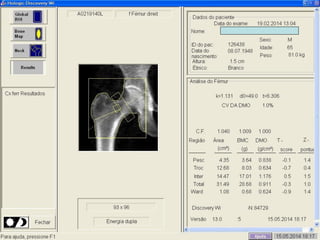

Aquisição (posicionamento)

Análise